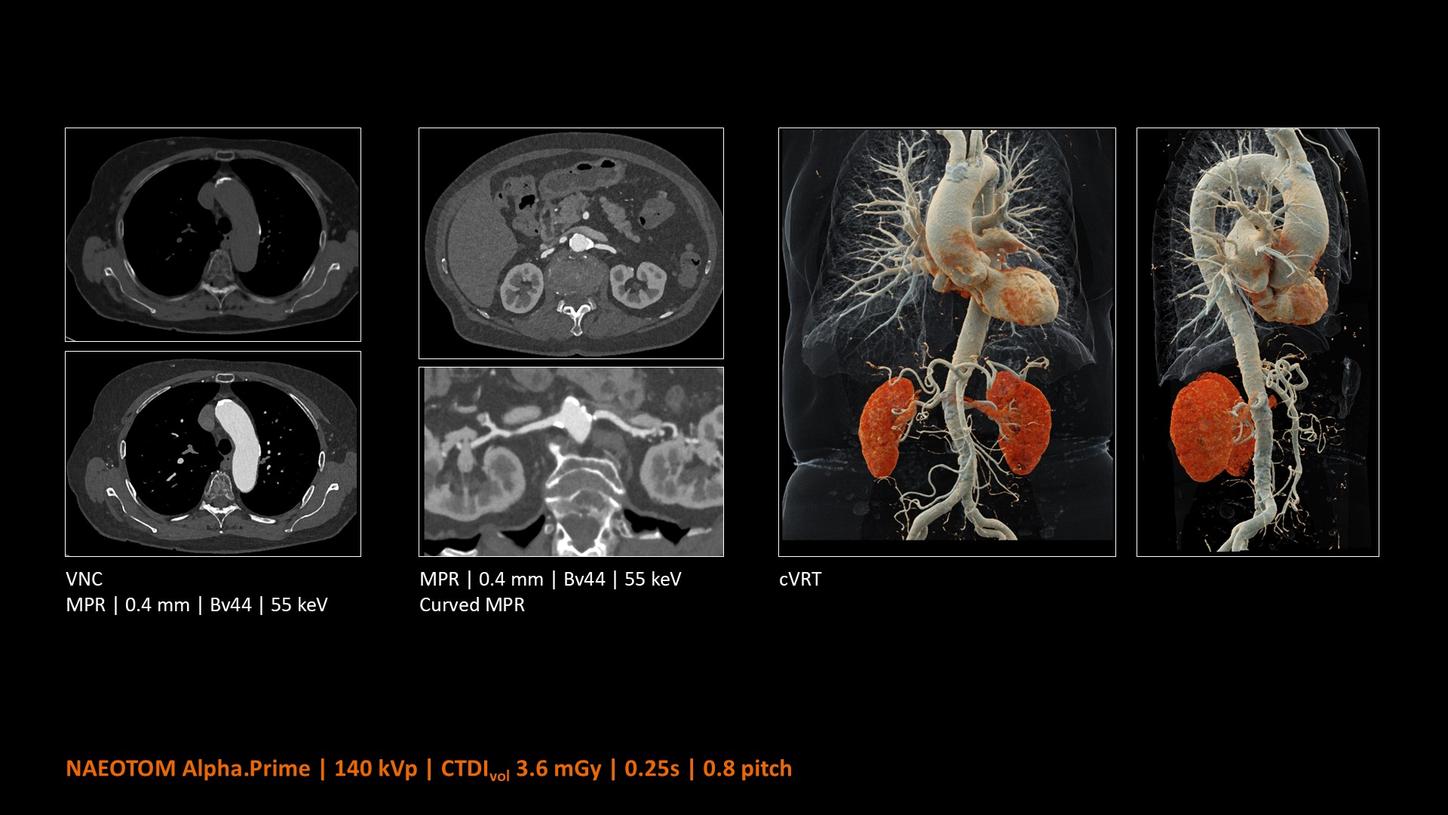

NAEOTOM Alpha® con Quantum Technology®, la nostra nuovissima Dual Source photon-counting CT, offre immagini Quantum HD Cardiac con uno spessore di slice di 0,2 mm. In questo modo è possibile visualizzare dettagli del cuore precedentemente non rilevabili senza incrementi di dose. Inoltre, le informazioni spettrali sono automaticamente disponibili in ogni scansione grazie a un processo di conversione diretta che trasforma i singoli fotoni dei raggi X in un segnale elettrico per creare l'immagine.

Quantum Technology consente una migliore valutazione diagnostica dei vasi coronarici nella TC. Secondo un recente studio, NAEOTOM Alpha e Quantum HD Cardiac potrebbero aver contribuito a ridurre la necessità di un'angiografia coronarica invasiva per il 54% dei pazienti nel rilevamento della malattia coronarica in una popolazione ad alto rischio.¹